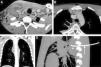

Un paciente de 21 años, que consultó por fiebre (39°C) y dolor cervical, presentaba una masa dolorosa en la región laterocervical derecha que se extendía desde la apófisis mastoides hasta el extremo medial de la clavícula. El paciente no tenía signos de faringoamigdalitis ni de otitis. En la analítica destacaba leucocitosis (29.000 leucocitos/mm3) y neutrofilia (80%). Una TC demostró una colección que afectaba al músculo esternocleidomastoideo derecho (fig. 1A) y que se extendía caudalmente hacia el mediastino anterosuperior (fig. 1B) y posterior (fig. 1C). Los abscesos del músculo esternocleidomastoideo y del mediastino anterosuperior fueron drenados quirúrgicamente después de realizar un drenaje percutáneo con control radiológico de la colección del mediastino posterior (fig. 1D). El análisis microbiológico confirmó una infección por Streptococcus pyogenes, presentando el paciente una excelente evolución.

A) Imagen axial de TC de cuello en la que se observa una colección (asterisco) en el seno del músculo esternocleidomastoideo derecho. B) Imagen axial de TC del tórax superior que muestra una colección en mediastino anterior (asterisco) y otra multiseptada en mediastino posterior (flechas). C) Reconstrucción coronal de TC de tórax en la que se aprecia mejor la extensión craneocaudal de la colección del mediastino posterior (asterisco). D) Reconstrucción sagital de TC de tórax en la que se identifica el drenaje tipo «pigtail» (flecha) liberado en el interior de la colección del mediastino posterior (asterisco).